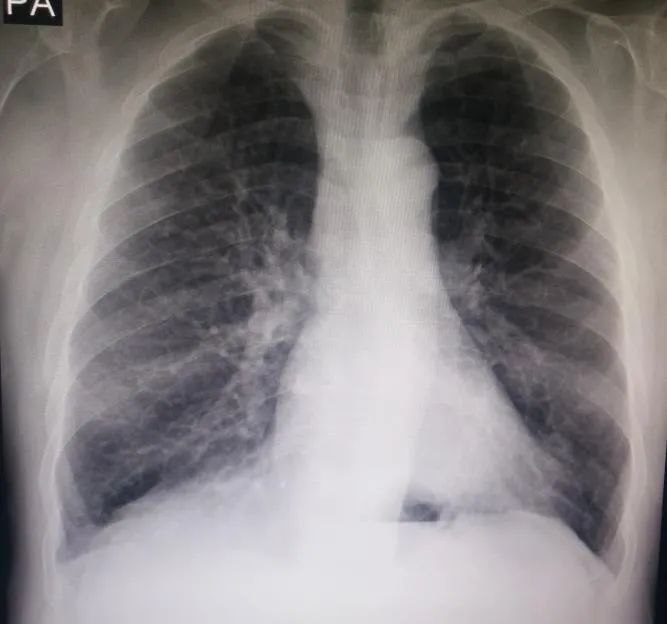

查体:体温38.5℃;心率94次/分,呼吸20次/分,血压110/60 mmHg。C反应蛋白(CRP):31mg/dL(正常值0-5mg/dL),白细胞8600/mm²,血沉10mm/h,胸片无异常(图1)。入院4天后出现失代偿性呼吸性酸中毒,无创机械通气治疗无效后转入重症监护室。

图1 入院时胸片